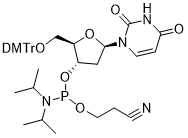

馬鞍山致研生物醫(yī)藥科技有限公司成立于馬鞍山市鄭浦港新區(qū)現(xiàn)代產(chǎn)業(yè)園。公司專(zhuān)注于生物小分子、醫(yī)藥中間體相關(guān)產(chǎn)品的研發(fā)和生產(chǎn),產(chǎn)品主要包括DNA亞磷酰胺單體、RNA亞磷酰胺單體、特殊單體以及按照客戶(hù)要求定制的RNA和DNA,并且公司提供定制合成等方面的研究服...

馬鞍山致研生物醫(yī)藥科技有限公司成立于馬鞍山市鄭浦港新區(qū)現(xiàn)代產(chǎn)業(yè)園。公司專(zhuān)注于生物小分子、醫(yī)藥中間體相關(guān)產(chǎn)品的研發(fā)和生產(chǎn),產(chǎn)品主要包括DNA亞磷酰胺單體、RNA亞磷酰胺單體、特殊單體以及按照客戶(hù)要求定制的RNA和DNA,并且公司提供定制合成等方面的研究服...